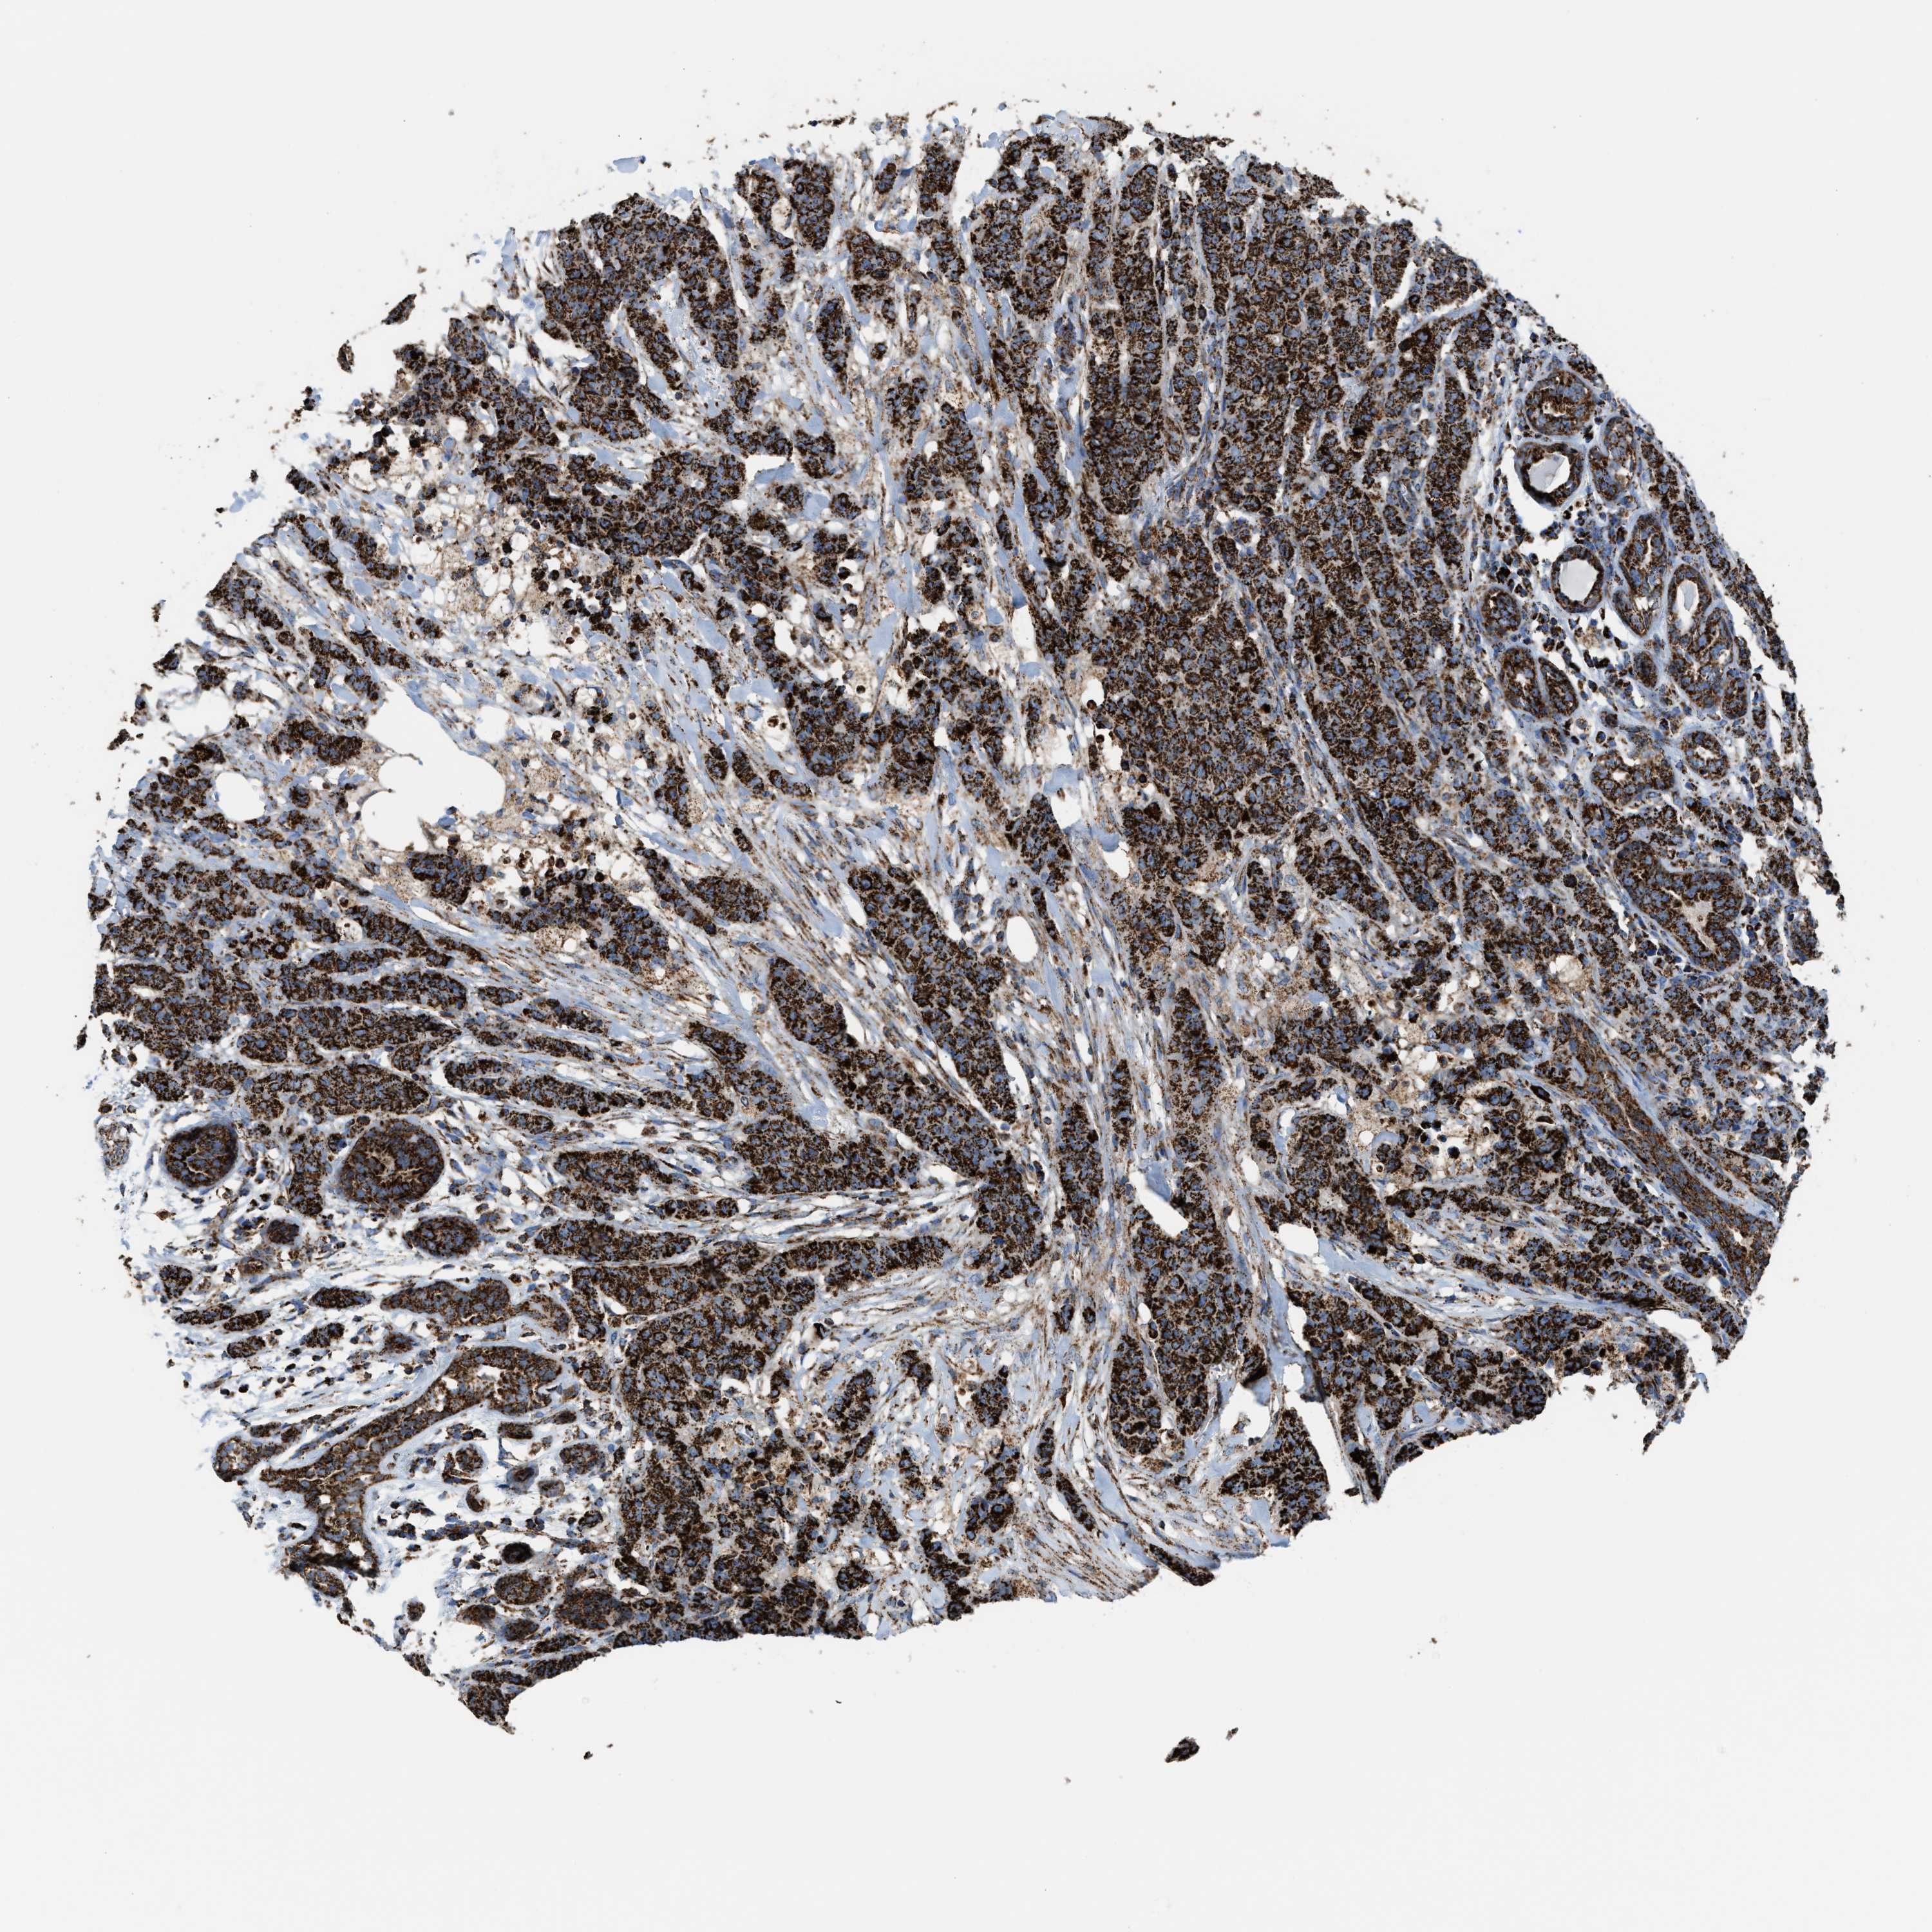

CANCER BREAST CANCER Show tissue menu

BRCA TCGA BRCA VALIDATION PROTEIN EXPRESSION

ANTIBODIES

AND

VALIDATION